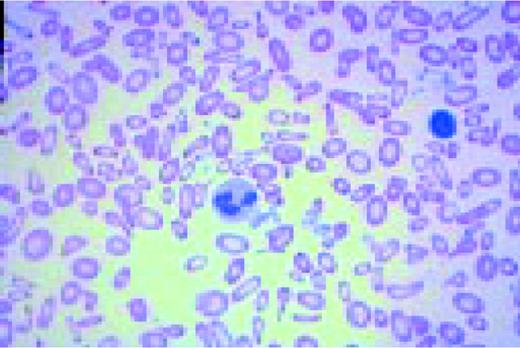

A normal peripheral blood lymphocyte and monocyte.FIG1